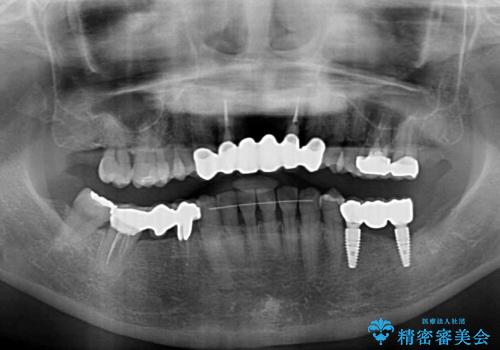

金属を使用した前歯のブリッジや奥歯の銀歯は全てオールセラミッククラウンまたはセラミックインレーとし、左下の奥歯はインプラントにより治療を行うこととしました。

外科処置を行うため、治癒を待つ期間が数ヶ月あるため、その期間を利用して下顎前歯のスペースを矯正治療で閉じることとしました。

遠方からの来院であったので、1回の治療時間を長めにし、できる限りの処置を集中して行うことで、来院回数を減らすことができました。

矯正治療までは考えていなかったそうですが、物が挟まっていた前歯のスペースがなくなり、矯正治療を行って良かったとのことでした。

初診カウンセリングを含めて13回の通院で治療を終えることができ、患者様には大変満足していただきました。